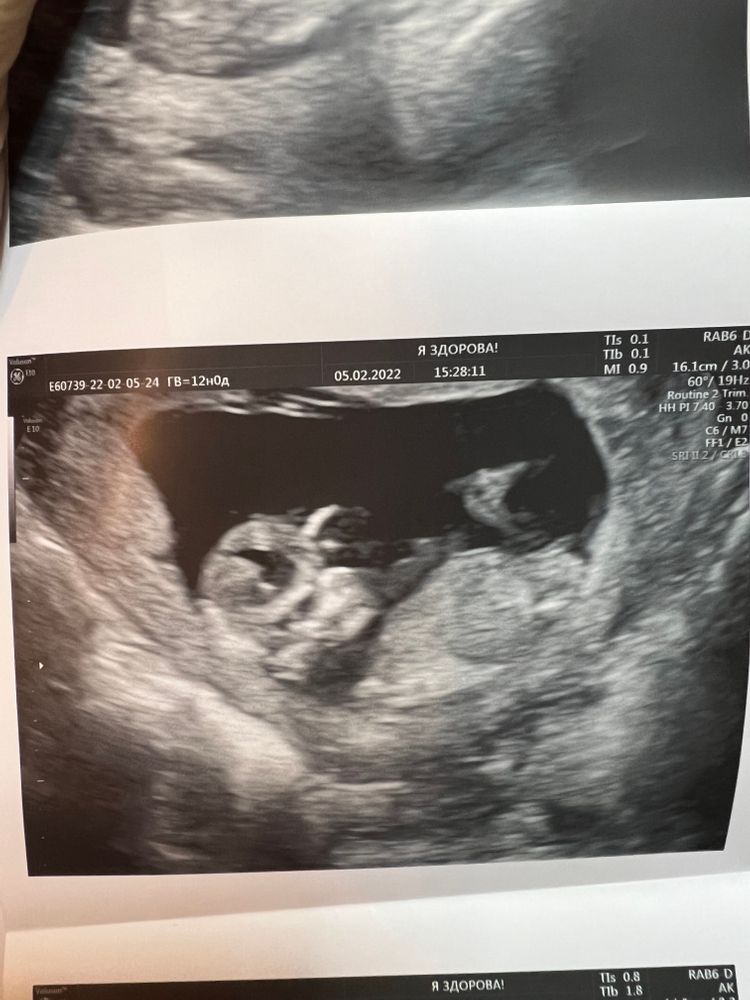

Кто проФи в распознавании пола?

Мне непонятно... Тут у Вас либо боком как-то, либо спиной малыш... Надо точно в профиль, и чтобы половой бугорок видно было хорошо. А если мальчик и девочка, то это круто просто)))

Юлия Sonnце, блин, а я думала тут боком…

Юлия Sonnце, а тут кто не знаете? это не бугорок? Изображение

Пол определяется не фото с узи, где видна одна голова и спина. Либо у вас ещё первый скриннинг и пол неясен, либо это уже узи на более позднем сроке, а узист не понимает ничего, тогда смените узиста.

Annie Zol, у меня 1 скрининг и узили сказала мальчик и девочка) просто я не пойму где кто) поэтому и выложила скрины! И если что, тут все так делают можете в поиске проверить, и в 50% случаях на первом скрининге все видно уже) если ктр больше 6см)

Annie Zol, на фото 12 недель, там написано. Но пол не видно из-за ракурса.